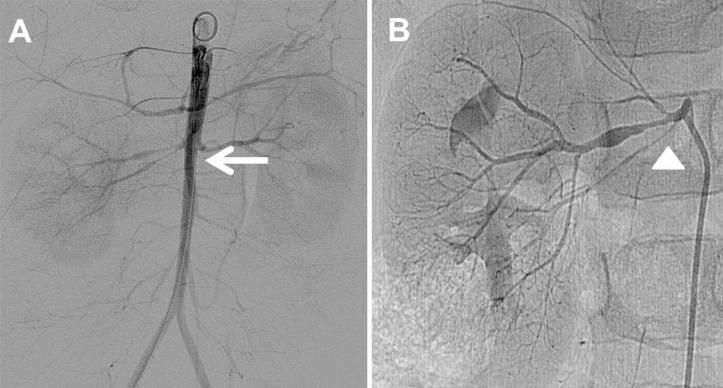

Midaortic syndrome (MAS) is a rare vascular disease that commonly causes renovascular hypertension. The lumen of the abdominal aorta narrows and the ostia of the branches show stenosis. MAS is associated with diminished pulses in the lower extremities compared with the upper extremities, severe hypertension with higher blood pressure in the upper rather than lower extremities, and an abdominal bruit. The clinical symptoms are variable, and recognition in children with hypertension can aid early diagnosis and optimal treatment. Hypertension with MAS is malignant and often refractory to several antihypertensive drugs. Recently, radiologic modalities have been developed and have led to numerous interventional procedures. We describe the case of a 3-year-old boy presenting with left ventricular hypertrophy whose severely elevated blood pressure led to the diagnosis of idiopathic MAS. This case highlights the importance of measuring blood pressure and conducting a detailed physical examination to diagnose MAS. This is the first reported case of idiopathic MAS diagnosed in childhood in Korea.

中段主动脉综合征(MAS)是一种罕见的血管疾病,通常会导致肾血管性高血压。腹主动脉管腔变窄,分支开口处出现狭窄。与上肢相比,MAS与下肢脉搏减弱、上肢血压高于下肢的严重高血压以及腹部杂音有关。临床症状多变,对高血压儿童的识别有助于早期诊断和最佳治疗。MAS所致高血压为恶性,通常对多种降压药物耐药。近年来,影像学技术不断发展,催生了众多介入治疗手段。我们描述了一名3岁男孩的病例,该男孩因左心室肥厚就诊,其严重升高的血压最终导致特发性MAS的诊断。该病例突出了测量血压和进行详细体格检查对诊断MAS的重要性。这是韩国首例报道的儿童期诊断的特发性MAS病例。